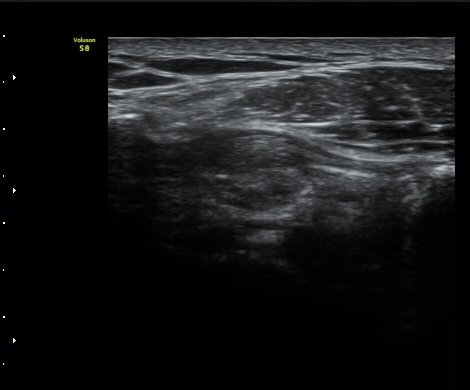

°ßºÀ¿À±¸µ¹±âÀδë Á¾´Ü¸é°Ë»ç¿¡¼­ ÀδëÀÇ ¿ÜÃø¿¡ ±¹¼ÒÀûÀÎ ÀÎ?ºñÈİ¡ °üÂûµÈ´Ù(»çÁø 3).